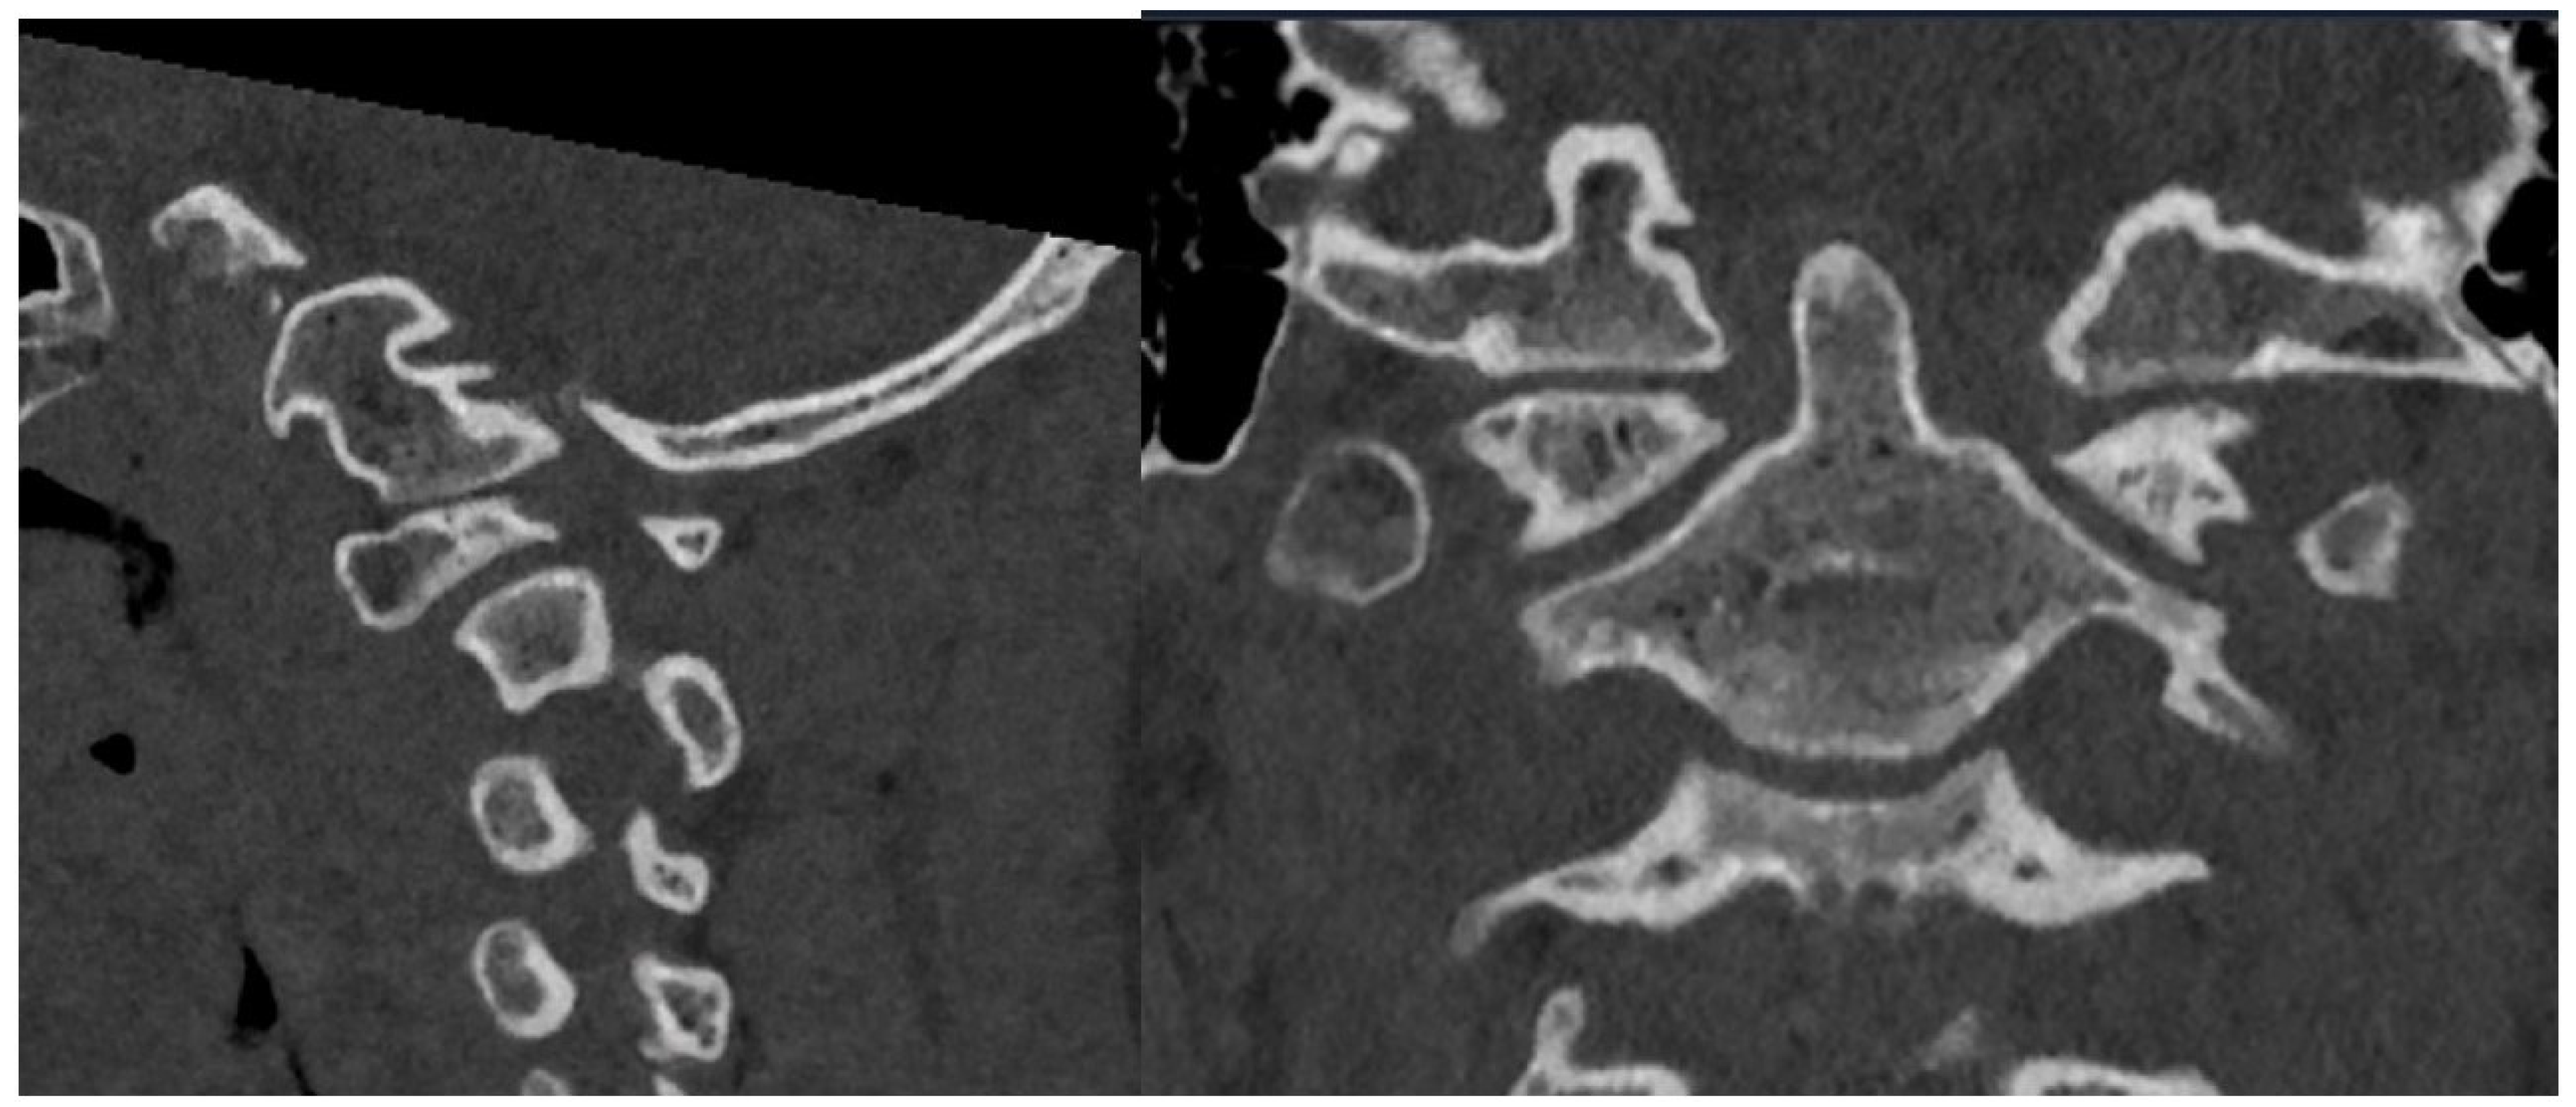

2.2. Imaging and Diagnosis